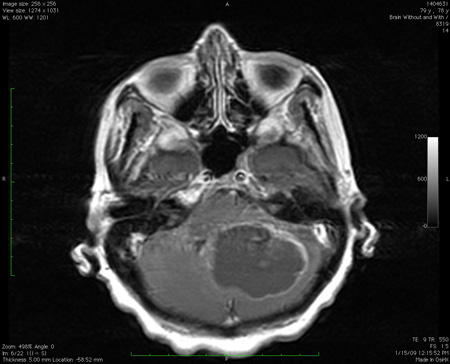

ნათხემში ვრცელი ფართობის დაზიანება წნევის ეფექტით, როგორც ჩანს მრი-ზე.

ექიმი ს.ჰ. საბრამონის კოლექციიდან; გამოყენებულია მფლობელის ნებართვით